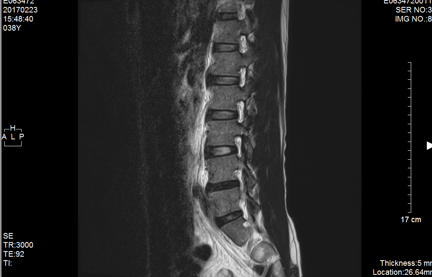

整形外科にてMRI検査では、軽い椎間板ヘルニアと診断される。